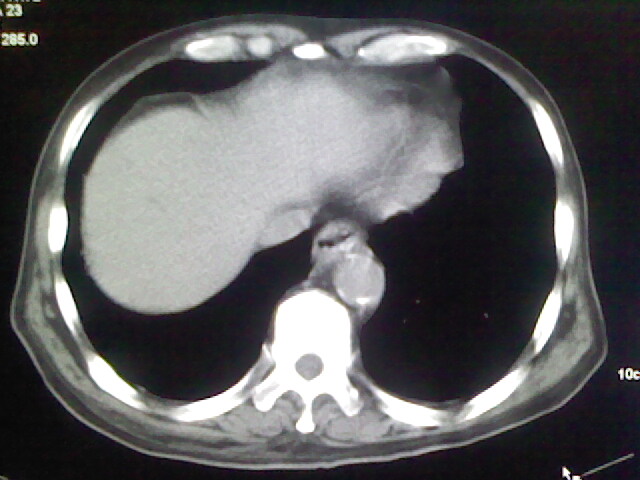

男,70岁,脑出血,长期卧床,左侧背部可触及肿块

肺部感染,背部筋膜增厚,考虑坠积性水肿或炎症

右侧肺部见片状密度增高影,边缘模糊。考虑炎症。另食管壁增厚。

食道里是什么

你放上去的